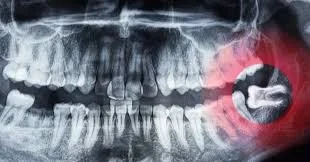

Wisdom Teeth Removal

Protect your smile’s alignment and prevent future complications with gentle, precise wisdom tooth extraction. Dr. Thomas ensures a smooth and stress-free experience using advanced surgical methods that minimize pain, swelling, and recovery time. Whether your wisdom teeth are impacted or just starting to cause discomfort, we provide the expert care you need for a healthy, pain-free recovery.